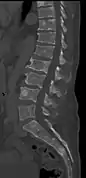

Illustration showing the most common site of bone lesions in vertebrae

Bone pain affects almost 70% of people with multiple myeloma and is one of the most common symptoms.[2]:653[22] Myeloma bone pain usually involves the spine and ribs, and worsens with activity. Persistent, localized pain may indicate a pathological bone fracture. Involvement of the vertebrae may lead to spinal cord compression or kyphosis. Myeloma bone disease is due to the overexpression of receptor activator for nuclear factor κ B ligand (RANKL) by bone marrow stroma. RANKL activates osteoclasts, which resorb bone. The resultant bone lesions are lytic (cause breakdown) in nature, and are best seen in plain radiographs, which may show "punched-out" resorptive lesions (including the "raindrop" appearance of the skull on radiography). The breakdown of bone also leads to the release of calcium ions into the blood, leading to hypercalcemia and its associated symptoms.[23]